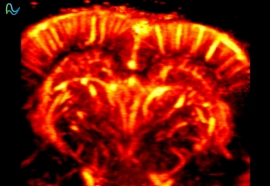

脑功能成像